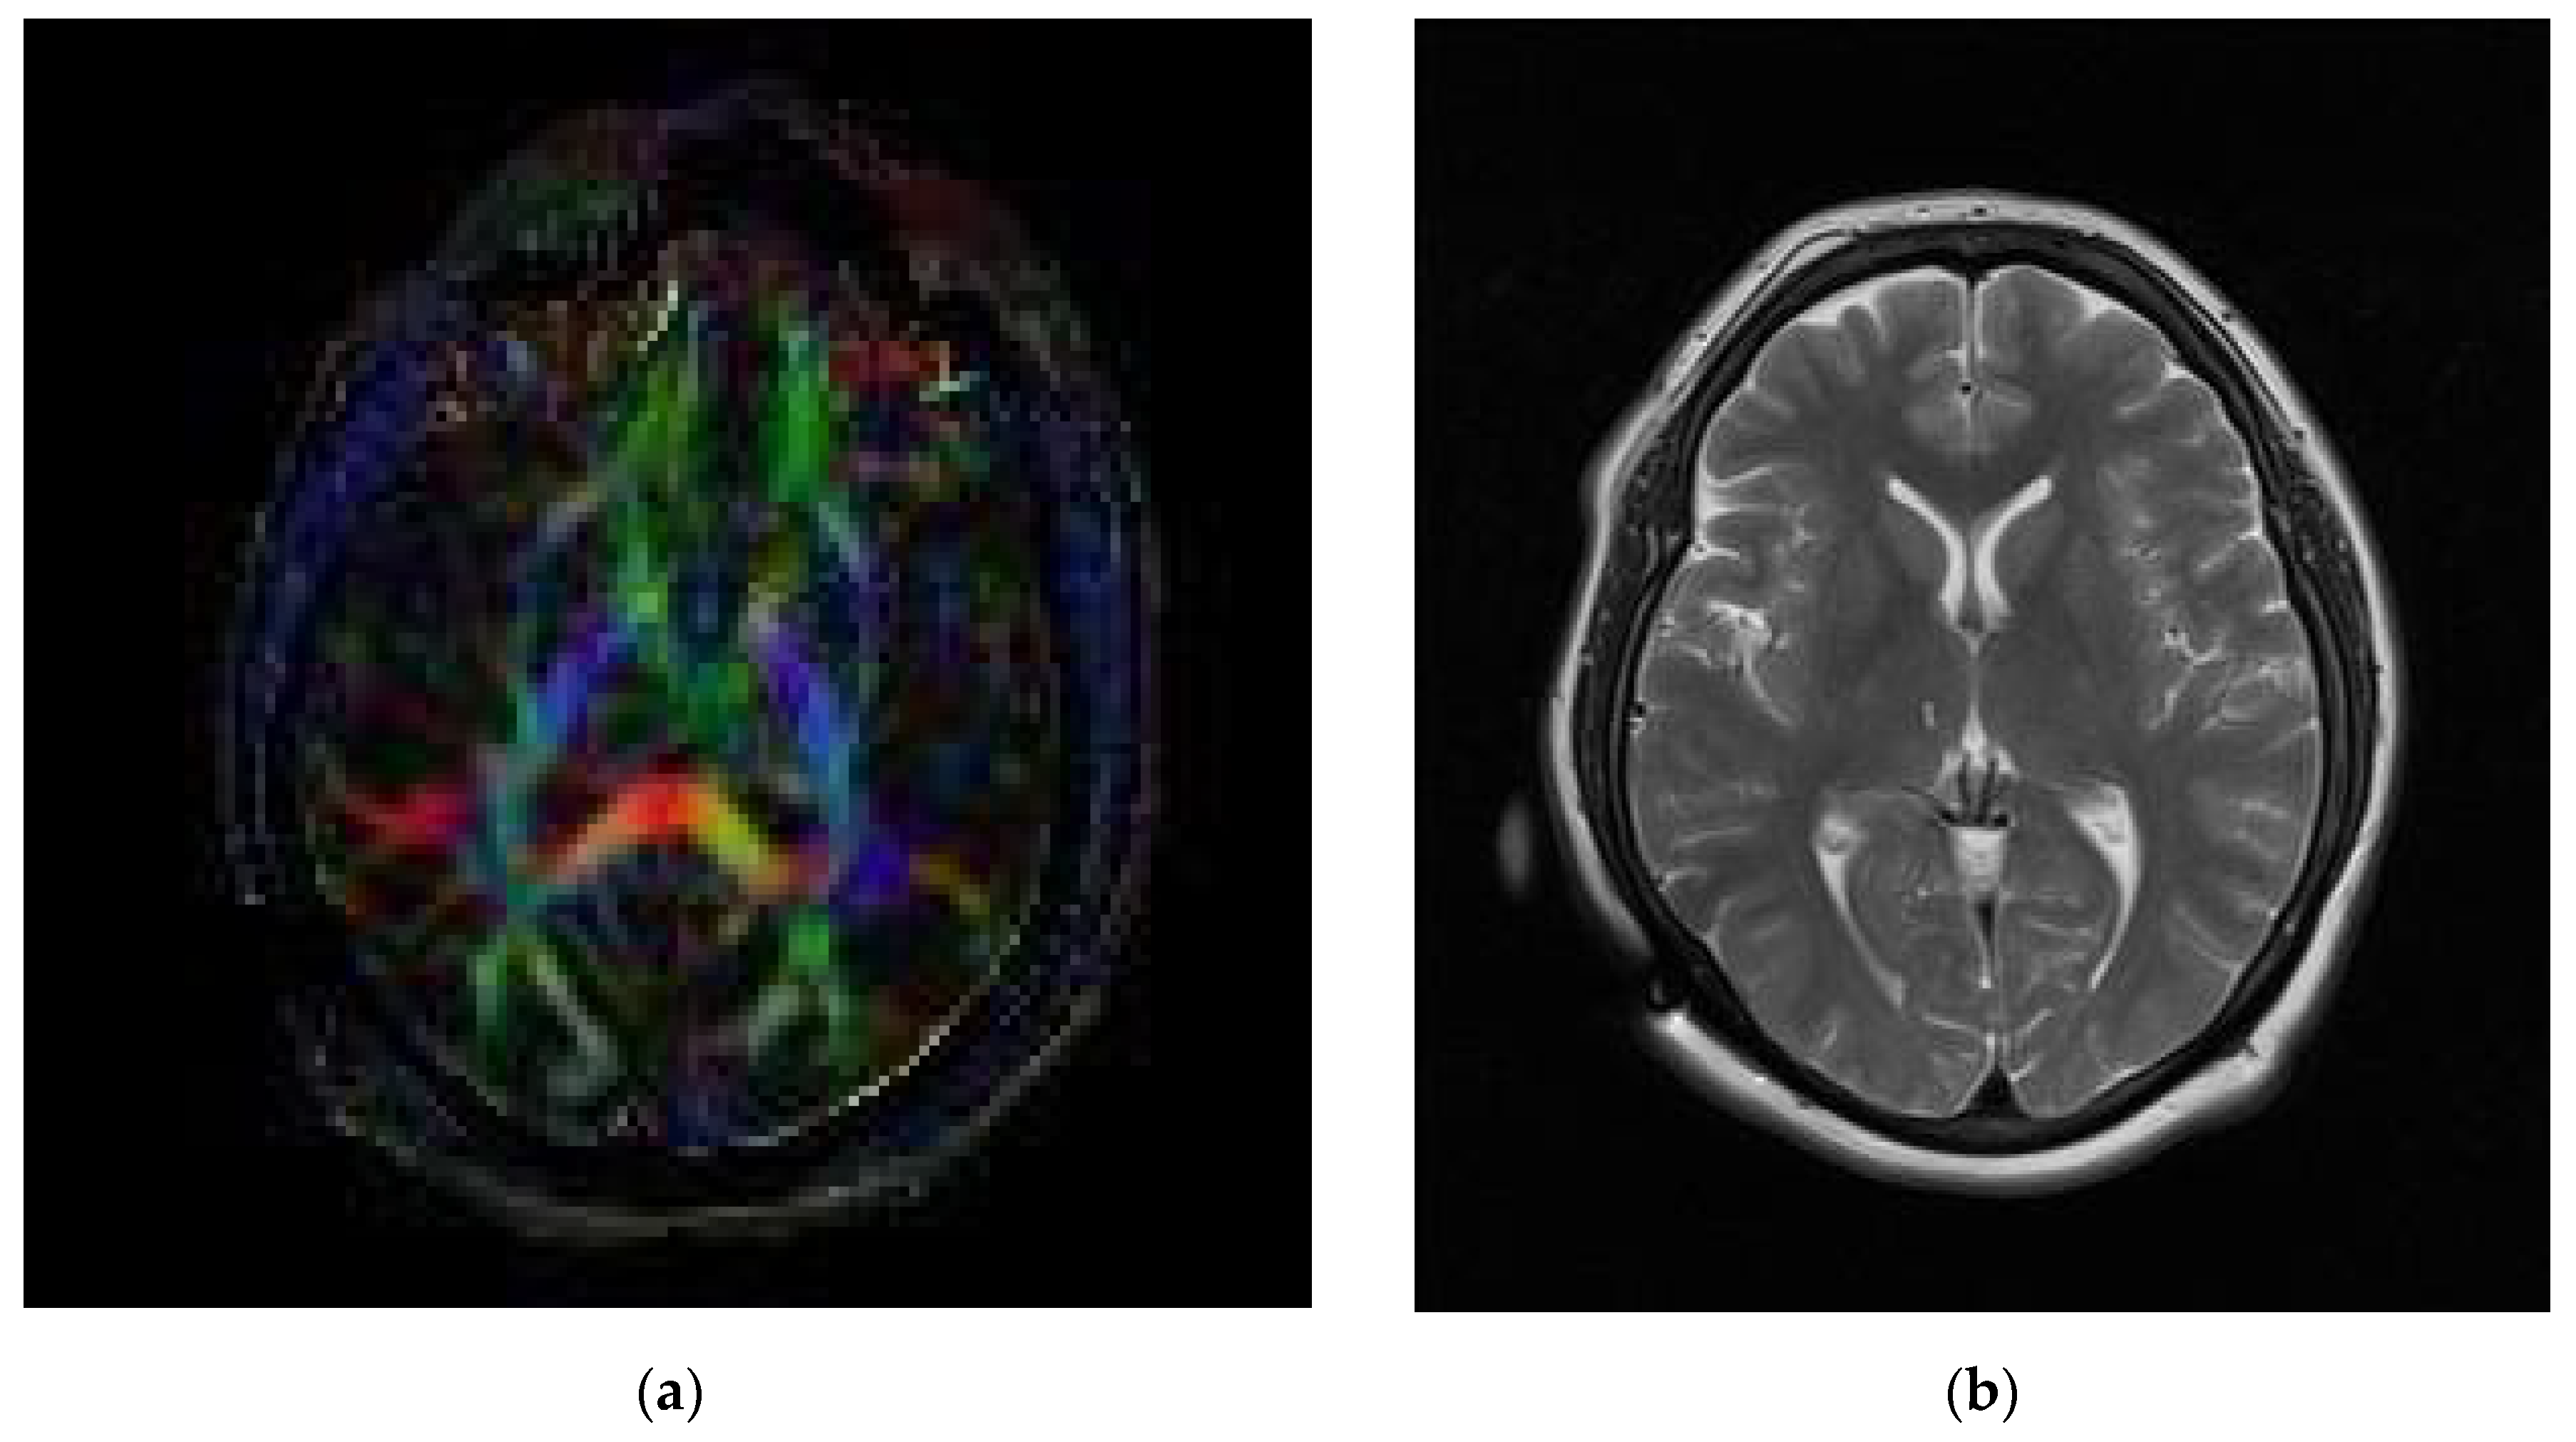

2. Case Presentation

Surgical Technique